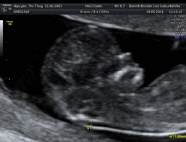

* First Trimester Screening. Messung der Nackentransparenz, Nasenbein, Combined Test (12.-14. SSW) - hier Termin vereinbaren!

2. Organscreening idealerweise in der 22.-24. SSW - hier Termin vereinbaren!